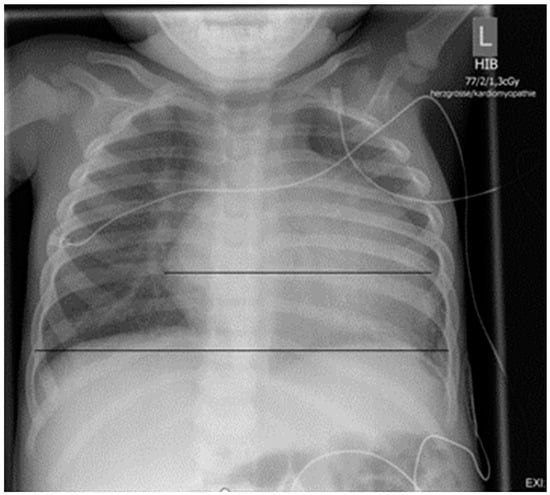

In order to investigate for reasons of the observed shortness of breath, an X-ray examination of the thorax was performed, which revealed a clearly enlarged cardiac silhouette (Figure 2). Additional laboratory test of cardiac biomarkers revealed elevated NT-proBNP of 14258 pg/mL (norm: <320 pg/mL), while Troponin was normal.

Figure 2.

Chest X-ray on admission: cardiac silhouette is clearly enlarged (HTQ 0.64).